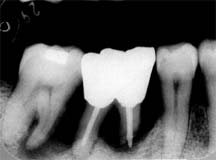

│6根管治療時 │4急激な骨破壊が認められる

既往歴:

初診は '83年(27歳)で、当時から臼歯部の歯槽骨破壊が認められ、歯周疾患進行傾向の高いことが 推測された。手術を含む歯周疾患治療の必要性を再三説明したにも関わらず、患者さんの理解を得る ことができなかった。'96年再来時までの13年間に3度程来院しているが、いずれも主訴に対する 治療とスケーリングを行っただけである。

'96年来院時に、上顎左右の臼歯を失うに至りようやく歯周疾患治療の必要性を認識し、 手術を行わないことを前提に歯周疾患治療を同意した。 以来、1年間症状も安定し順調にコントロールできたかのように思われていたが、突如、│4 の動揺を訴えて来院。レントゲン診査の結果、同部の急激な骨破壊を認めた。

│4の歯髄は壊死状態で、いわゆる“上行性歯髄炎”と診断され、抜髄ののち、 │456の連結固定を行う予定である。